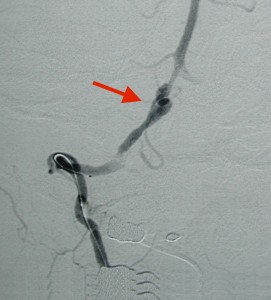

<コイル塞栓術後:右椎骨動脈を動脈瘤ごとコイルで閉塞>

<コイル:矢印>